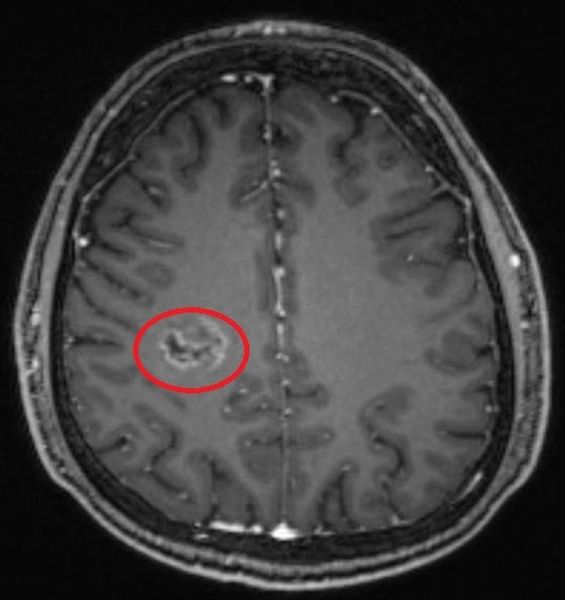

Демиелинизирующие заболевания мозга: МРТ изображения